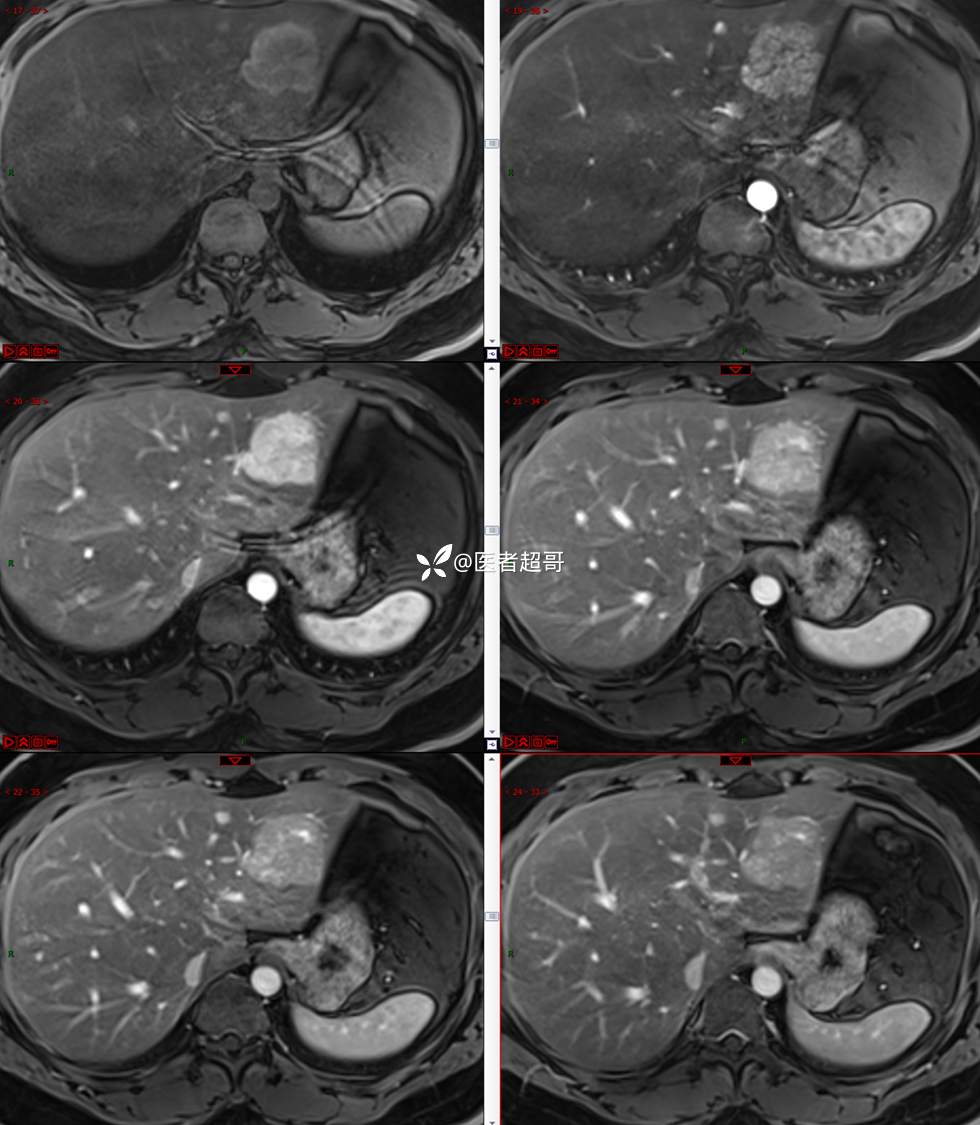

【影诊笔记685】男,31y,发现肝占位性病变5天就诊,请诊断分析,有病理结果!

主 诉:发现肝占位性病变5天。

现病史:患者缘于5天前体检时发现肝占位性病变,未予以特殊处置。现患者为求系统诊治就诊于我院,行普美显提示:肝左叶富血供占位,请结合临床及其他检查,肝多发血管瘤,脂肪肝,肝囊肿,请结合临床。门诊以“肝占位性病变”收入我科。病程中,饮食睡眠可,二便可,近期体重未见明显变化。